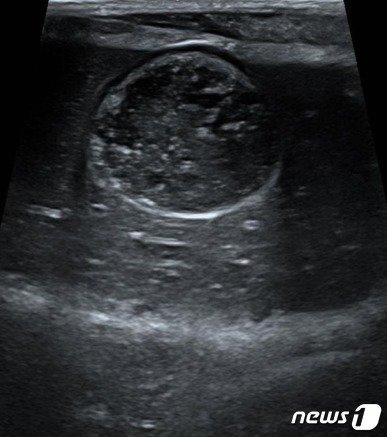

본문 이미지 - 담낭점액종 초기 증상을 보인 강아지 초음파 사진(VIP동물의료센터 성북점 제공) ⓒ 뉴스1

담낭점액종 초기 증상을 보인 강아지 초음파 사진(VIP동물의료센터 성북점 제공) ⓒ 뉴스1